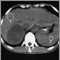

Adrenal metastases, CT scan

Adrenal Tumor - CT